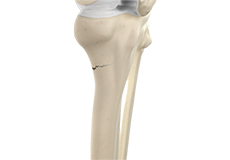

Bones of the Knee

The knee is a hinge joint made up of two bones, the thighbone (femur) and shinbone (tibia). There are two round knobs at the end of the femur called femoral condyles that articulate with the flat surface of the tibia called the tibial plateau. The tibial plateau on the inside of the leg is called the medial tibial plateau and on the outside of the leg, the lateral tibial plateau.

The two femoral condyles form a groove on the front (anterior) side of the knee called the patellofemoral groove. A small bone called the patella sits in this groove and forms the kneecap. It acts as a shield and protects the knee joint from direct trauma.

A fourth bone called the fibula is the other bone of the lower leg. This forms a small joint with the tibia. This joint has very little movement and is not considered a part of the main joint of the knee.